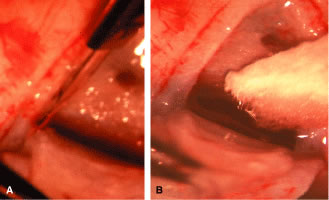

the 10 and 2 o'clock positions of the eye, assumes great significance.  Fig. 9. Indentation gonioscopy. A. The angle appears closed. However, the observer cannot determine whether

this appearance is due to mere contacts between the iris and cornea

or to actual adhesion. B. The goniolens has been pressed against the central cornea, displacing

aqueous into the periphery and showing that the angle is open. C. Indentation gonioscopy displaces the iris posteriorly, showing peripheral

anterior synechiae. (Schwartz LW. Diagnostic evaluation of the patient. In Spaeth GL (ed). Early

Primary Open-Angle Glaucoma: Diagnosis and Management. Boston: Little, Brown & Co, 1979.) Fig. 9. Indentation gonioscopy. A. The angle appears closed. However, the observer cannot determine whether

this appearance is due to mere contacts between the iris and cornea

or to actual adhesion. B. The goniolens has been pressed against the central cornea, displacing

aqueous into the periphery and showing that the angle is open. C. Indentation gonioscopy displaces the iris posteriorly, showing peripheral

anterior synechiae. (Schwartz LW. Diagnostic evaluation of the patient. In Spaeth GL (ed). Early

Primary Open-Angle Glaucoma: Diagnosis and Management. Boston: Little, Brown & Co, 1979.)